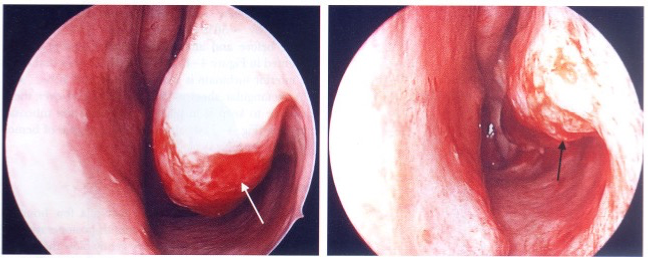

Turbinate Hypertrophy

Causes

• Infection

• Compensation

• Dysfunctional

• Allergies